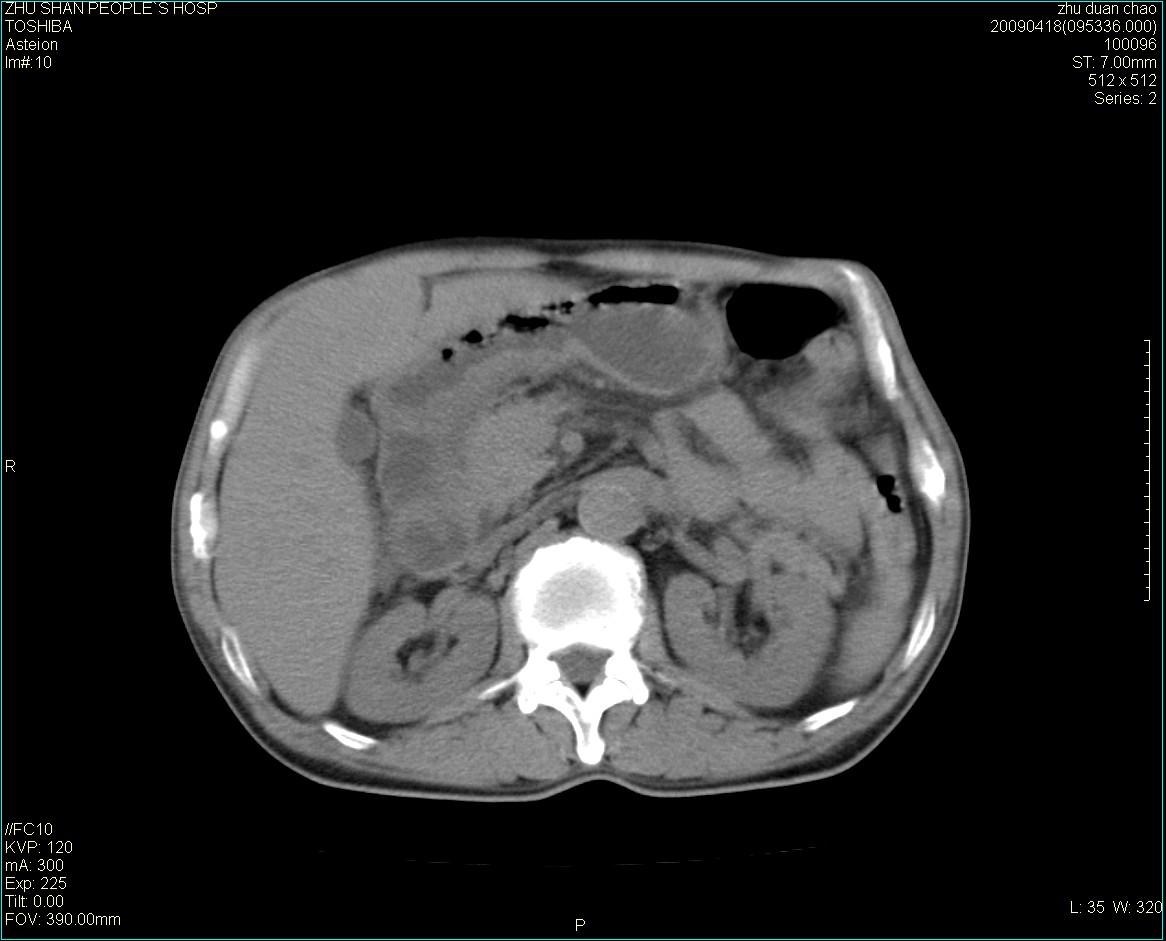

以下是引用余辉在2009-4-22 10:48:00的发言:[br]结肠肝曲附近肠段包块,病灶密度不均匀,周围肠系膜脂肪混浊,见多枚淋巴结肿大,考虑结肠癌可能性大,病灶累及范围较广建议进一步检查除外其他

以下是引用随光逐影在2009-4-22 11:57:00的发言:[br]考虑肠道肿瘤(间质瘤?)可能性大。

以下是引用ydx_74在2009-4-22 14:39:00的发言:[br]结肠癌周围侵犯可能,不能完全除外炎性病变